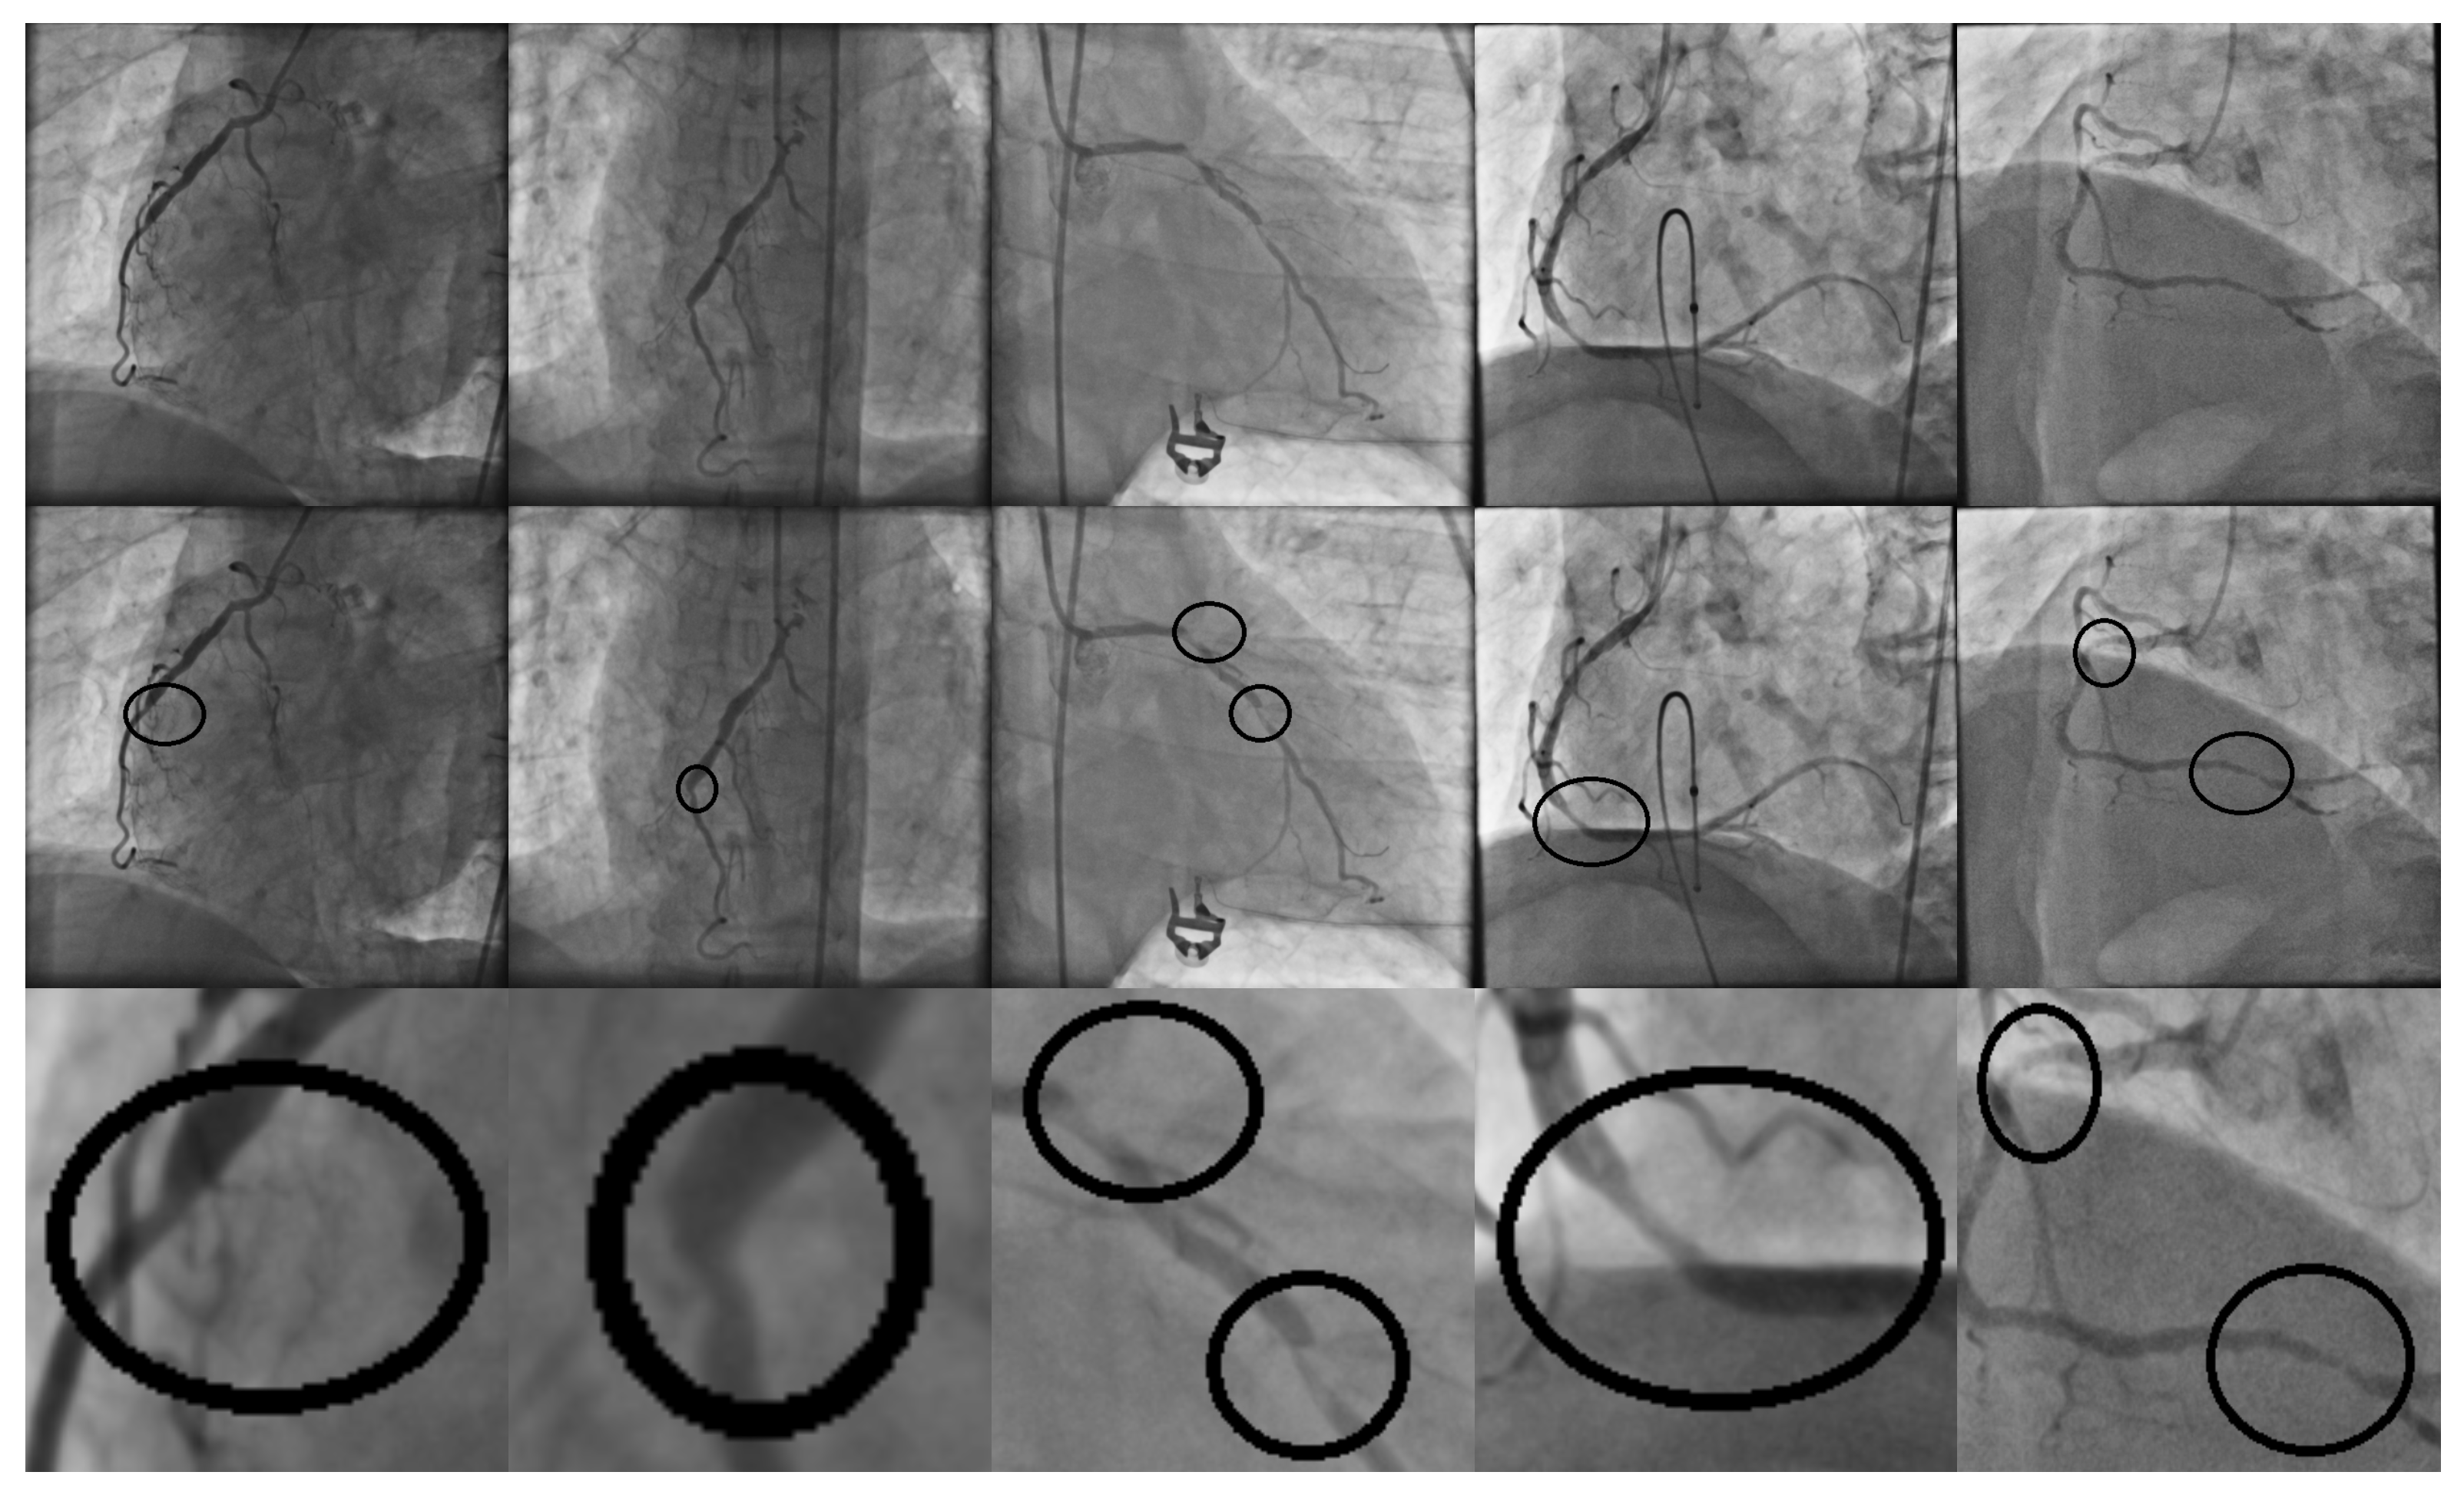

2. Materials and Methods

2.1. Experiment Materials